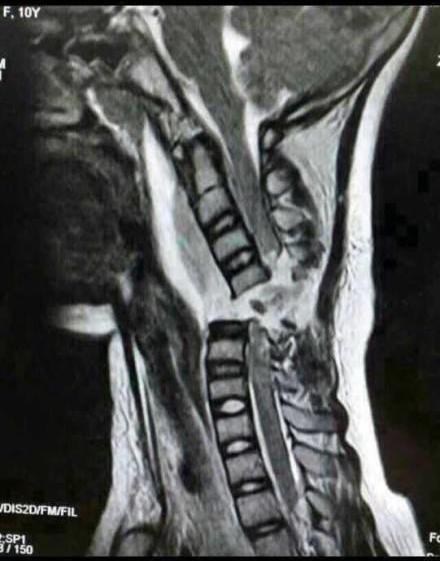

微信朋友圈,很多人都在為這位10歲的小姑娘祈禱。這就是她頸椎完全斷裂的圖片。

12月2日下午,她戴著長圍巾乘坐電動車時,長圍巾被車輪絞住。在慣性作用下,小青的脖子被緊緊勒住,電動車停下後,她感覺自己不能動了,而且呼吸也變得非常困難。經過手術,小青終於脫離危險,但由於脊柱斷裂,小青已全身癱瘓。同時,意外還影響到了肌肉,小青已不能自主呼吸,目前只能通過呼吸機輔助呼吸。